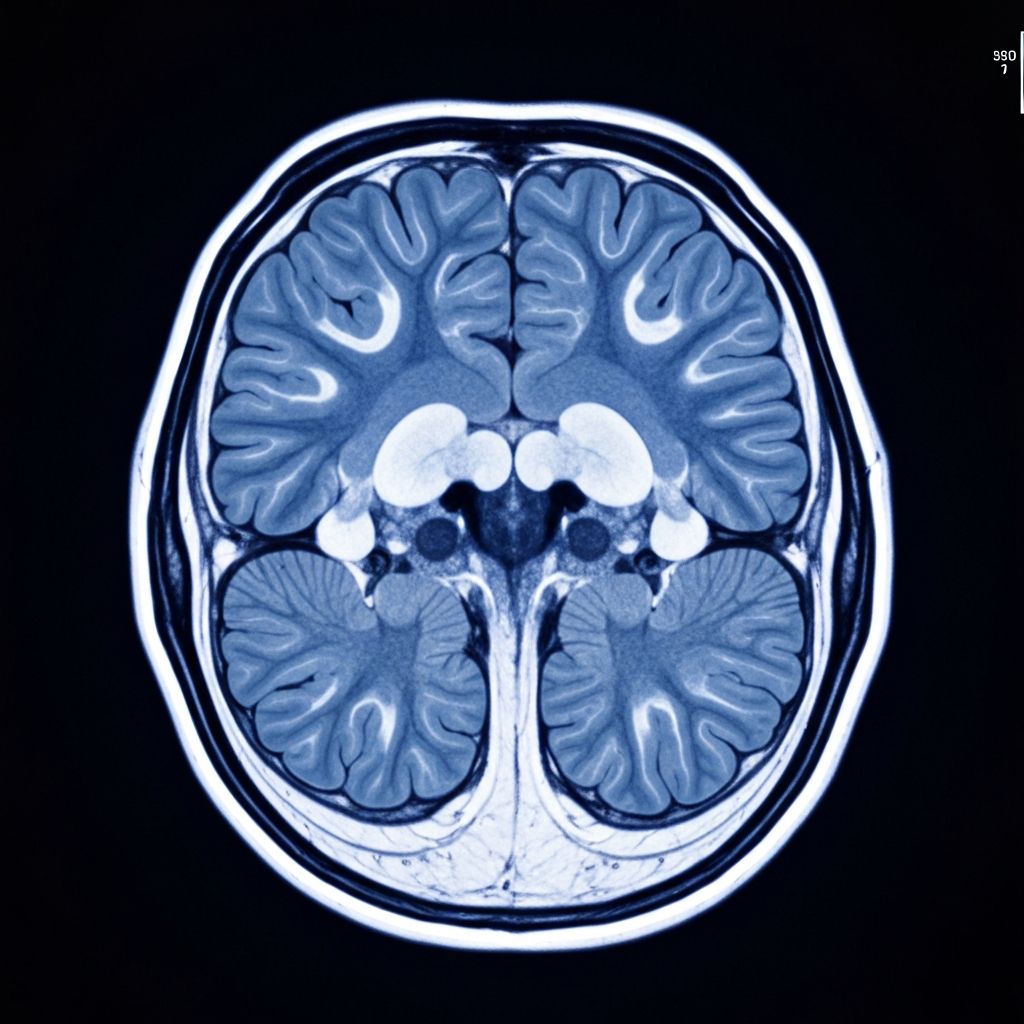

- Ressonância magnética com contraste: Padrão-ouro para diagnóstico